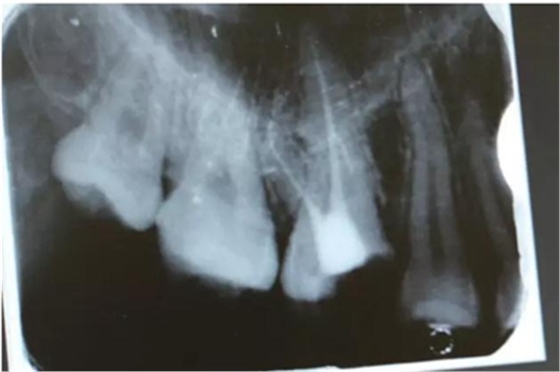

病例一 女性,20歲,大學(xué)生,要求補牙,檢查口內(nèi)可見A6大面積缺損,近中牙齦息肉,拍X片,根管充填物略差,但根周未見明顯陰影,口內(nèi)檢查無叩痛。建議患者冠延長手術(shù)+高嵌體修復(fù)。

患牙遠(yuǎn)中邊緣嵴完整,強度沒有降低,故擬保留遠(yuǎn)中邊緣嵴,高嵌體修復(fù)。首先去除腐質(zhì)及原墊底材料,流體樹脂+3M Z350XT樹脂墊底。局麻下行冠延長手術(shù)。在此需要提及個人的一個觀點。冠延長手術(shù)原則上要求3-6個月以上才能永久修復(fù)。但是個人喜歡后牙肩臺建立在齦上,所以修復(fù)后的修復(fù)體邊緣位于牙齦上方1mm,對牙周的愈合影響較小(如果為齦下邊緣則要慎重),故該患者術(shù)中按照齦上邊緣的設(shè)計進行冠延長手術(shù)。以下為術(shù)中: